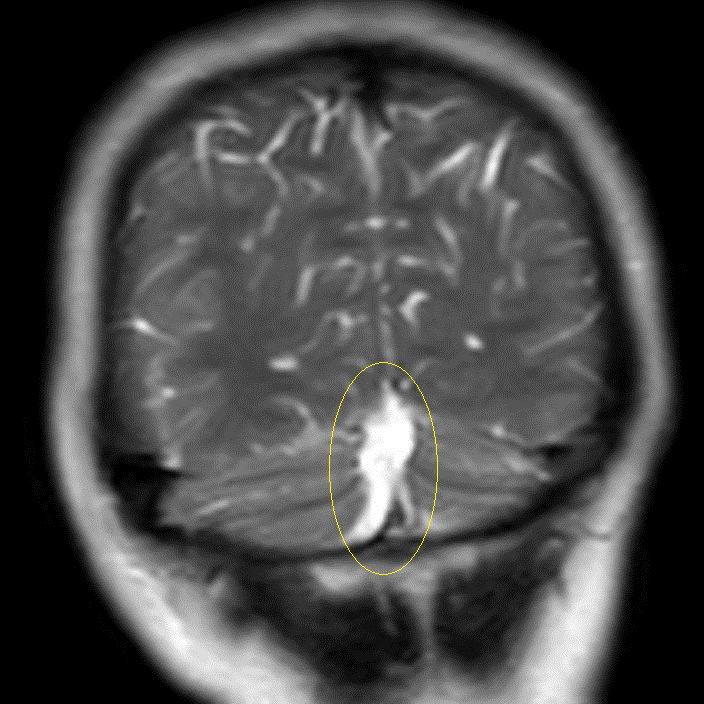

Внутричерепная гипотензия: КТ-исследования и их интерпретация

Раздел: Образы вокруг